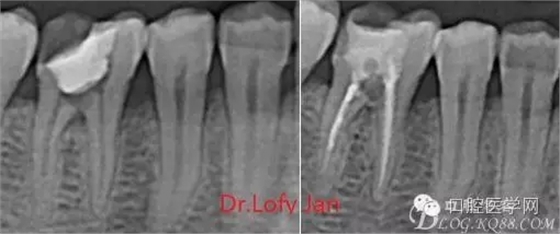

根管治療術(shù)是牙體牙髓疾病治療中最復雜和最關(guān)鍵的治療項目。根管充填材料抵達根尖、并能嚴密堵塞根尖孔,是確保根管治療效果的關(guān)鍵指標。為了保證根管充填到位,醫(yī)生需要在術(shù)前照牙片以了解牙根根管的數(shù)量、彎曲程度和長度,在術(shù)中有時需要插針照牙片來精確測量根管長度,術(shù)后必須照牙片以確定是否根管充填到位,如果欠填或超填,就需要重新充填、重新照牙片確認,直到根管充填到位。所以,在患者接受根管治療時有時會反復照牙片。

病例分析:曲面斷層片在x線輔助診斷與檢查中目前大多數(shù)文獻和著作都建議只能作為初診拍片檢查手段,不能作為終末疾病的確診與手術(shù)療效的評價指標,臨床大部分中小型門診都因為設備不齊全導致信息偏差很大。